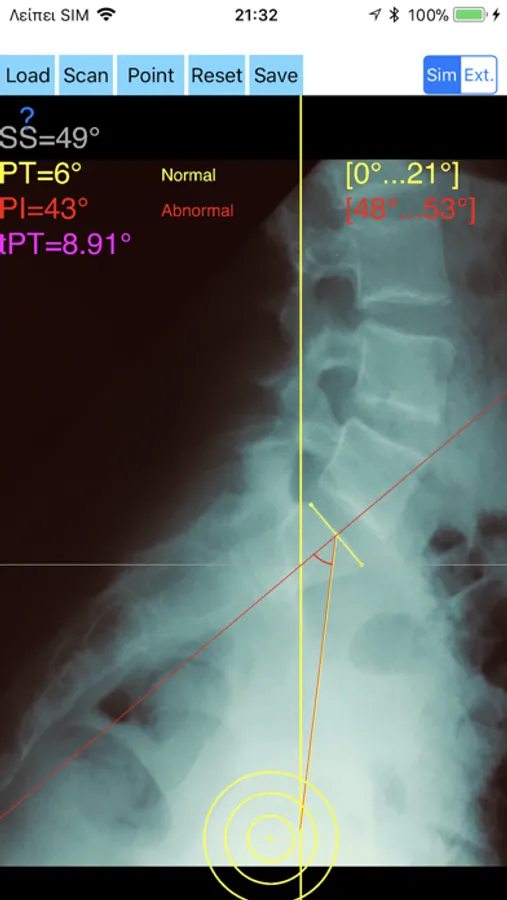

-By marking few points at the image of X-ray, the App calculates and offers a very convenient way to determine the most accurate possibly way at once, Pelvic incidence (PI), Sacral slope (SS), Pelvic Tilt (PT), Lumbar lordosis (LL), thoracic kyphosis, PI–LL Pelvic incidence Angle (PI) minus Lumbar lordosis Angle (LL) PI–LL, theoretical normal pelvic tilt (tPT),theoretical normal L1-S1 lumbar lordosis (tL1S1), Pelvic Radius Angle (PRA). According to measured parameters the app categorises the severity of the imbalance of spine, in different stages: optimal or non optimal.